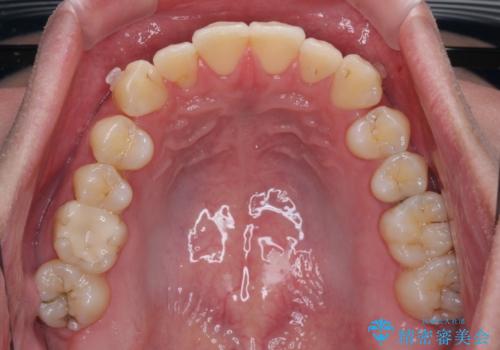

上下のデコボコを治したい インビザラインによる矯正治療

- 前歯のデコボコと突出感を気にして来院された患者様です。

極力目立たない装置を希望とのことで、インビザラインを用いて非抜歯で矯正治療を行うこととしました。

事前に親知らず4本を抜歯し、多少歯列を後方に移動できるように準備をした上で、なるべく歯と歯の間を削ることなくデコボコを解消できるように計画しました。

途中、以前大きなむし歯で処置をした歯が痛み出し、根管治療が必要となったため、根管治療とオールセラミッククラウンによる補綴治療を行い、その後にインビザラインによる仕上げの歯列移動を行い、無事に治療を終えることができました。